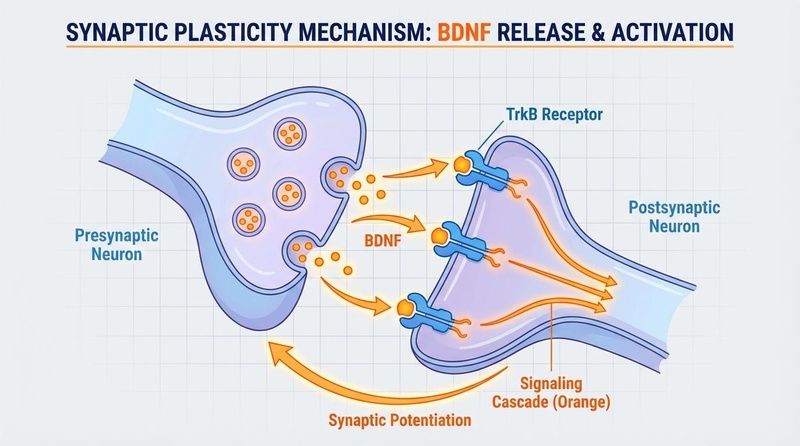

Exercise is arguably the most potent natural stimulus for neuroplasticity, mediated primarily by Brain-Derived Neurotrophic Factor (BDNF).

Exercise induces the release of BDNF, which strengthens synaptic connections and supports learning.

- BDNF Response: A single bout of high-intensity exercise moderately increases BDNF (Hedges’ g = 0.46), priming the brain for learning immediately post-workout. Regular training amplifies this response (Hedges’ g = 0.59), sensitizing the brain to neurotrophic signaling and promoting long-term structural changes[4].

Noopept is a peptide-derived compound (often grouped with racetams) that is highly potent (10-30mg dose). It modulates acetylcholine and AMPA receptors and increases HIF-1 (Hypoxia-Inducible Factor) and BDNF expression, aiding in memory consolidation and neuroprotection[22].

- ACD856: A novel positive allosteric modulator of Trk-receptors (Neurotrophin receptors). It enhances the signaling of BDNF and NGF, aiming to improve synaptic plasticity and memory.

- Semax: A synthetic peptide derived from a fragment of ACTH. Users report improved selective attention, memory consolidation, and a "clear-headed" stimulation. Critically, Semax does not deplete catecholamines. It rapidly upregulates the expression of BDNF and NGF in the hippocampus[32][33].